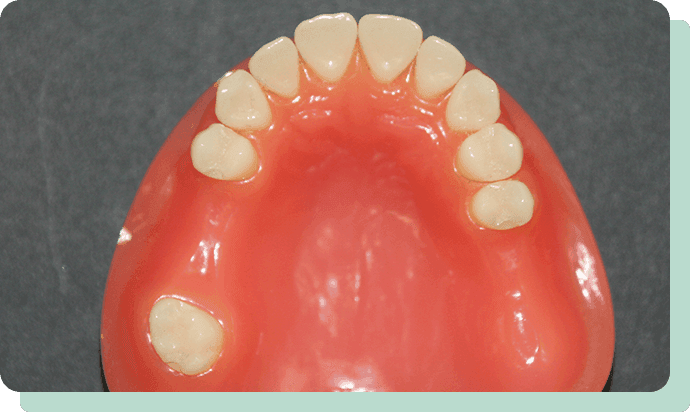

ノンスクラプデンチャーとは、バネが無い、新素材の入れ歯のこと。従来の部分入れ歯から、“クラスプ”といわれる金属のバネをなくしたもので、つけているのがわからないぐらい自然で美しく、付け心地も良い新世代の入れ歯です。

当クリニックが採用しているのは、品質と技術に徹底的にこだわった最高レベルのノンクラスプ義歯です。

参考模型